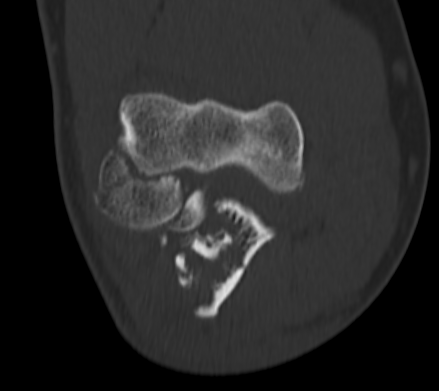

Orthopedic Surgeon with special interest in joint preservation